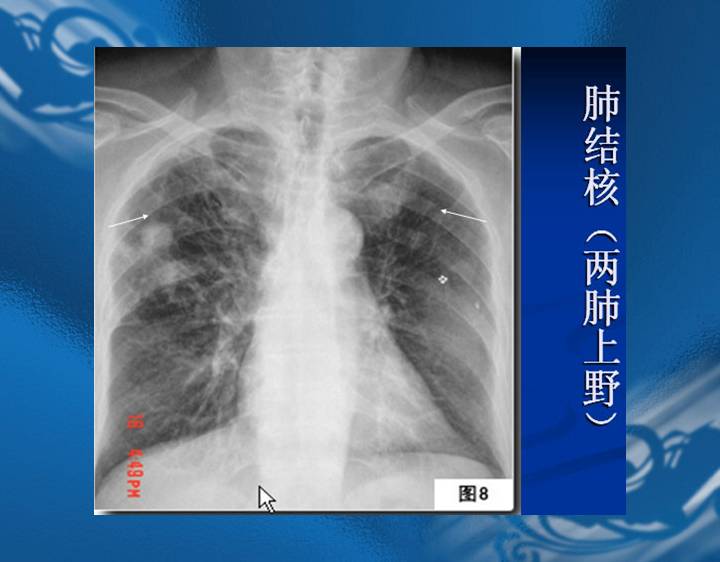

执业医师资格考试“实践技能”影像学辅导资料